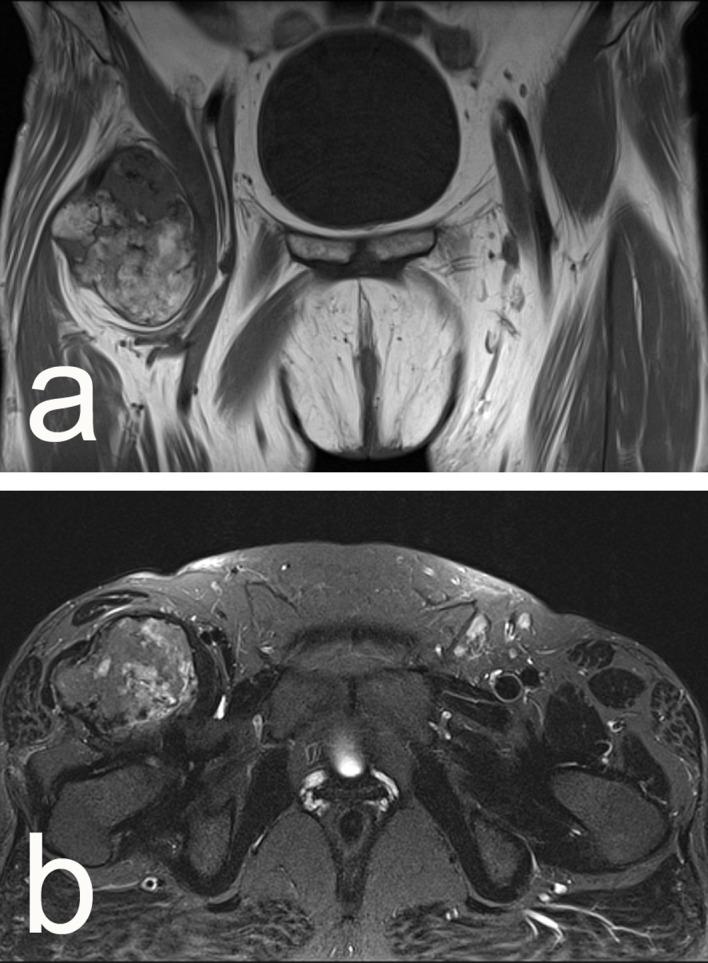

Osteochondromas, occurring usually in the metaphyses of long bones, are among the most frequent benign musculoskeletal neoplasms and both their sporadic and hereditary variants have been studied extensively. Extraskeletal osteochondromas, however, are much less common. They have been shown to arise near joints or synovial spaces of feet, hands, or bursae. Herein, we present a very rare case of an extraskeletal osteochondroma within the iliopsoas muscle.

骨软骨瘤通常发生于长骨的干骺端,是最常见的良性肌肉骨骼肿瘤之一,其散发型和遗传型均已得到广泛研究。然而,骨外骨软骨瘤则较为少见。已证实它们多发生于足、手的关节或滑膜腔附近,或滑囊处。在此,我们报告一例极为罕见的髂腰肌内骨外骨软骨瘤病例。